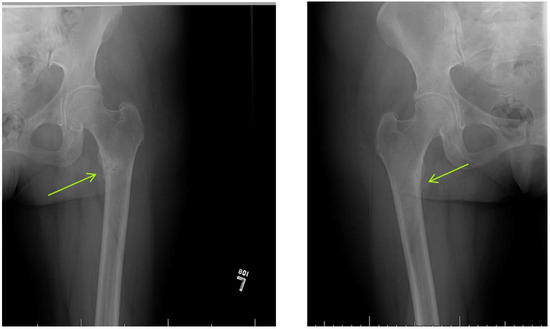

- Mateo, L.; Holgado, S.; Mariñoso, M.L.; Pérez-Andrés, R.; Bonjoch, A.; Romeu, J.; Olivé, A. Hypophosphatemic osteomalacia induced by tenofovir in HIV-infected patients. Clin. Rheumatol. 2016, 35, 1271–1279. [Google Scholar] [CrossRef]

- Parsonage, M.J.; Wilkins, E.G.L.; Snowden, N.; Issa, B.G.; Savage, M.W. The development of hypophosphataemic osteomalacia withmyopathy in two patients with HIV infection receivingtenofovir therapy. HIV Med. 2005, 6, 341–346. [Google Scholar] [CrossRef] [PubMed]